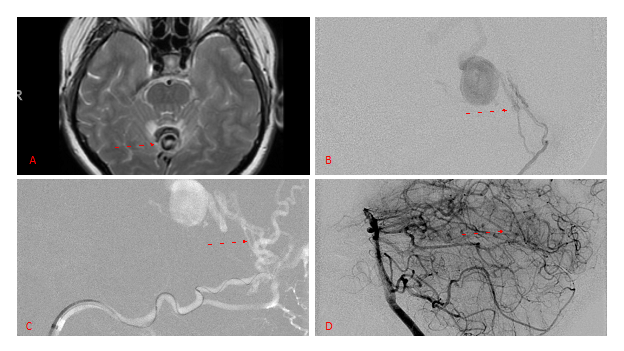

Figure 4. Left ECA AP and Lateral angiograms Pre (A and B) and Post NBCA embolization (C and D) Demonstrate near complete obliteration of Left Occipital Artery Fistulas.